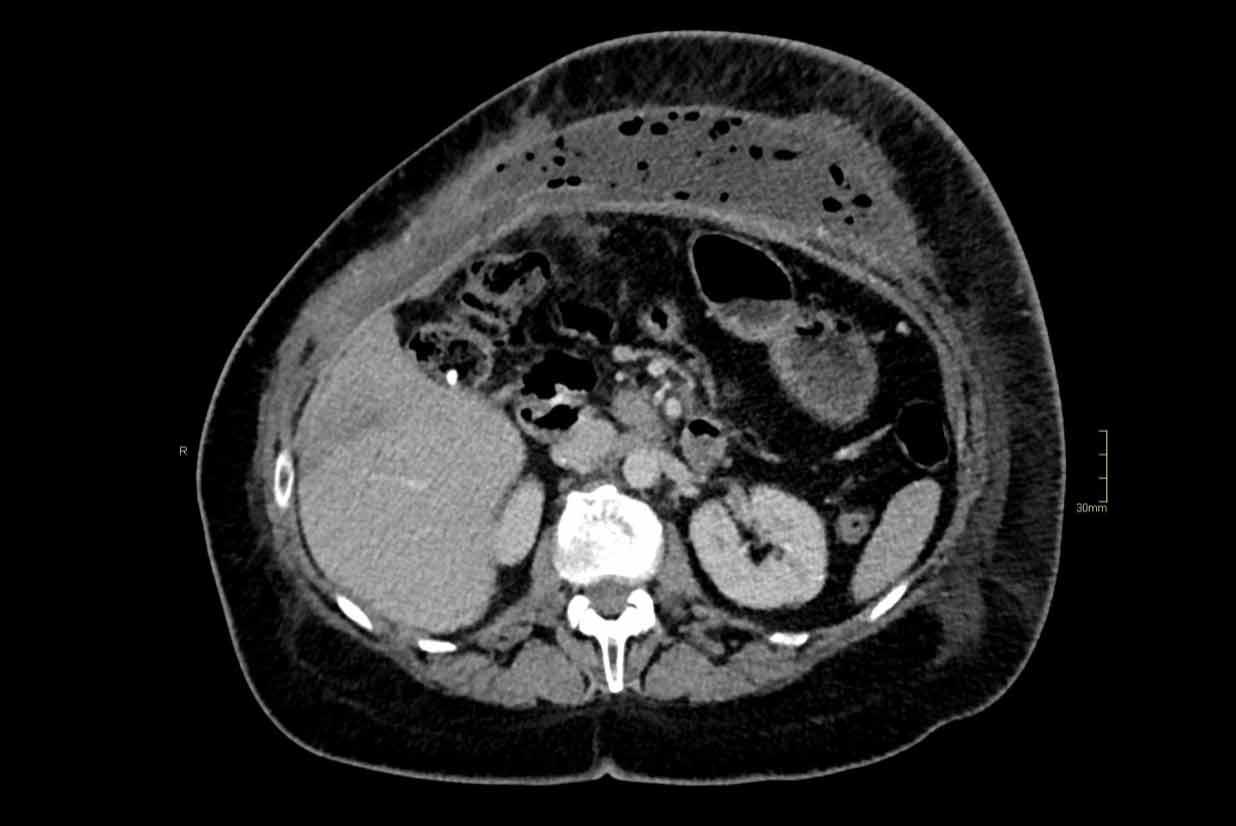

Phân ly cơ thẳng bụng là tình trạng giãn rộng khoảng cách giữa cơ thẳng bụng trái và phải, kèm theo thoát vị mỡ nội tạng hoặc quai ruột (hình minh họa).

Điểm khác biệt so với thoát vị là trong phân ly cơ thẳng bụng không có khiếm khuyết cân mạc.

Khoảng cách > 2,0 cm giữa cơ thẳng bụng trái và phải được coi là phân ly cơ thẳng bụng.

Ngoài chiều rộng theo mặt phẳng ngang, cần đo thêm chiều dài theo trục đầu-đuôi của vùng phân ly.

Phân ly cơ thẳng bụng ở nam giới thường do tăng mỡ nội tạng, còn ở nữ giới thường do thai kỳ.

Thoát vị thành bụng có thể cùng tồn tại với phân ly cơ thẳng bụng.

Phân ly cơ thẳng bụng cần được đề cập vì tỷ lệ tái phát thoát vị cao hơn khi có kèm theo tình trạng này.